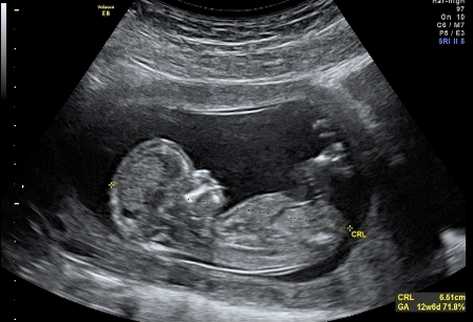

Un diagnóstico sacudió las  ilusiones de Celeste y su esposo. Poco antes del tercer mes de embarazo, un malestar la llevó anticipadamente a la consulta médica y al hospital.

“Tiene rubeola”, le dijeron. Y le explicaron las probables secuelas que tendría esa enfermedad viral en el bebé. Posible ceguera, problemas cardíacos o en la formación de algunos órganos.

La sintomatología confirmaba el pronóstico médico. Celeste se encontró ante la disyuntiva de abortar o tener al niño.

En efecto, se dictaminó con certeza que no se trataba de la temida  enfermedad. Su bebé está a salvo y ella se ha recuperado de la urticaria que padeció por varios días. Se alegra de haberlo pensado tanto.